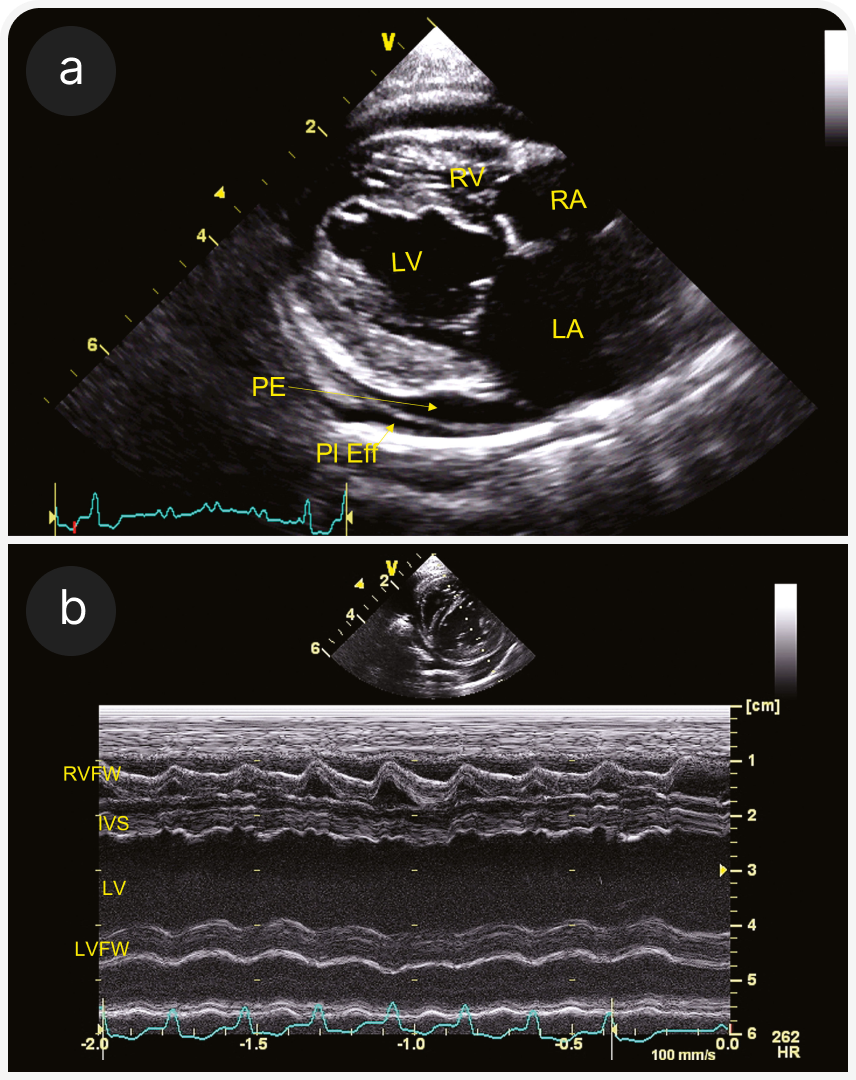

(а) Парастернальная четырехкамерная проекция справа (RPS) по длинной оси; визуализируются плевральный (pleural effusion) и небольшой перикардиальный выпот (pericardial effusion). Левое предсердие субъективно расширено.

(b) Четырехкамерная проекция справа (RPS) по длинной оси; видны B-линии за границей перикард-легкие (стрелки). Это гиперэхогенные радиальные линии, проходящие через легочную ткань; они показывают смесь воздуха и жидкости в легочной паренхиме. Их также можно оценить на УЗИ легких вне тени сердца. На этом изображении левое предсердие субъективно расширено.